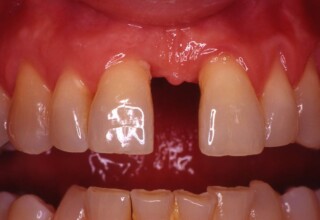

Restoration of bilateral diastemas between central and lateral incisors.

Diastemas were created mainly because of narrow laterals. After orthodontic treatment was finalized, the diastemas were closed with two composite resin restorations.